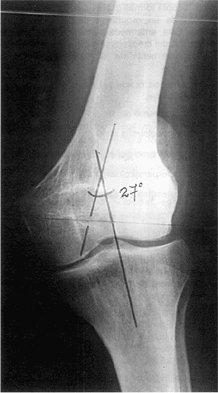

RADIOGRAFICAMENTE

Las alteraciones que nos llaman la atención son las epifisiarias. Estas están ensanchadas y en el caso de las rodillas con un valgismo de 27° recordando como aceptable, el valgo de 10° ó. funcional.

Control de rodilla izquierda pre-quirúrgico el 1 de agosto de 1991

El cartílago de conjunción ensanchado se continúa en dirección a la diáfisis con una zona osteoporóticá o tejido osteoide en metáfisis de la tibia, por lo que se decide realizar la osteotomía varizante a nivel femoral.

Las cortesas óseas están disminuidas tanto las femorales como las tibiales, como así también las trabeculas óseas de modo que determina el aspecto de "vidrio esmerilado". Las falanges distales de las manos presentan resorción ósea propio del hiperparatiroidismo.